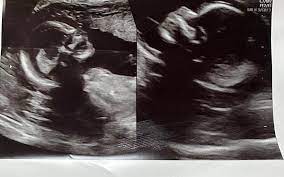

Amerika Birleşik Devletleri’nin (ABD) Alabama eyaletinde üç çocuk annesi 32 yaşındaki Kelsey Hatcher, doğuştan çift rahmi olduğunu ve her iki rahminde de bebek beklediğini açıkladı. Doktorlara göre bu, milyonda bir ihtimaldi.

32 yaşındaki Kelsey Hatcher, uterus didelphys ya da iki rahim olarak adlandırılan nadir bir rahim anomalisi ile doğdu. Ancak ilkbahar aylarına kadar bu durum fark edilmedi. Hatcher, iki rahim taşıdığını ve her ikisinden de çocuk sahibi olacağını öğrenince eşinin neredeyse kendisine inanmadığını ve “Yalan söylüyorsun” dediğini anlattı.

Bebeklerin çift yumurta ikizi olup olmayacağı belirsiz. Yerel haber kanalı WVTM’ye göre Hatcher’ın doğum tarihi Noel günü.